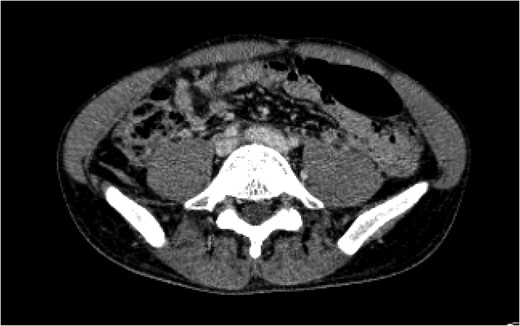

1). Given his hemodynamic stability, we consulted the vascular and interventional radiology teams regarding management. We decided to proceed with visceral arteriogram to control bleeding from the right kidney as well as a venogram to further delineate the suspected venous injury (Fig.

2).

Figure 2:

An interventional radiology angiogram and venogram on Day 1 showed a 2.8 cm pseudoaneurysm in the proximal portion of the left common iliac vein. There was no involvement of the base of the IVC and no active extravasation.